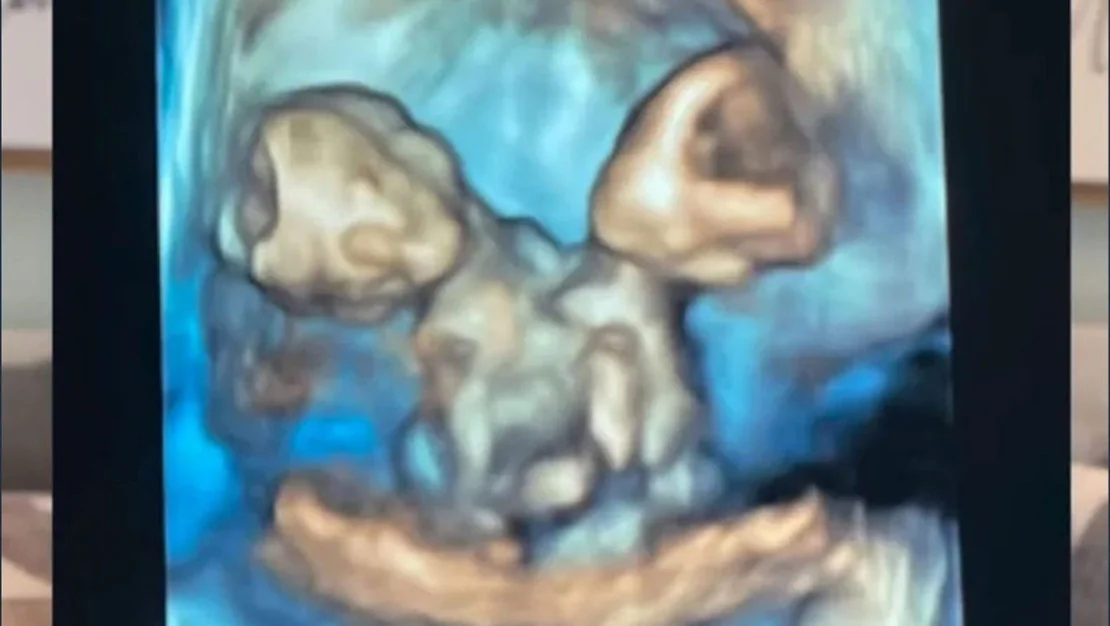

Nicole ve Austin LeBlanc çifti, Michigan eyaletinde ilk bebeklerine hamile olduklarını öğrenince büyük bir mutluluk duydu. Ancak bu mutlu haber, kısa süre içinde üzüntüye dönüştü. Gebeliğin yedinci haftasında yapılan kontrolde ultrasonda yalnızca bir kalp atışı duyulurken, ikiz gebelik olasılığı belirlendi. Çok geçmeden Nicole, şiddetli karın ağrısı nedeniyle hastaneye kaldırıldığında gerçekte hissettiği durum ortaya çıktı: Anne adayı, aynı kalbi, karaciğeri, bağırsakları, diyaframı ve göbek kordonunu paylaşan ikiz kız bebeklere hamileydi.

Nicole, 32. haftada sezaryenle ikizlerini dünyaya getirdi. Bebeklere Maria Therese ve Rachel Clare isimleri verildi ve doğum anında her biri farklı tepkiler verdi. “Maria yüksek sesle ağladı, Rachel ise uyuyordu. Yüzlerini görmek ve paylaştıkları bedene şahit olmak inanılmazdı” diyen anne, o anları gözyaşları içinde tarif etti. Ancak ne yazık ki bu ikizler, doğumdan çok kısa bir süre sonra anne ve babalarının kucağında hayata gözlerini yumdu…